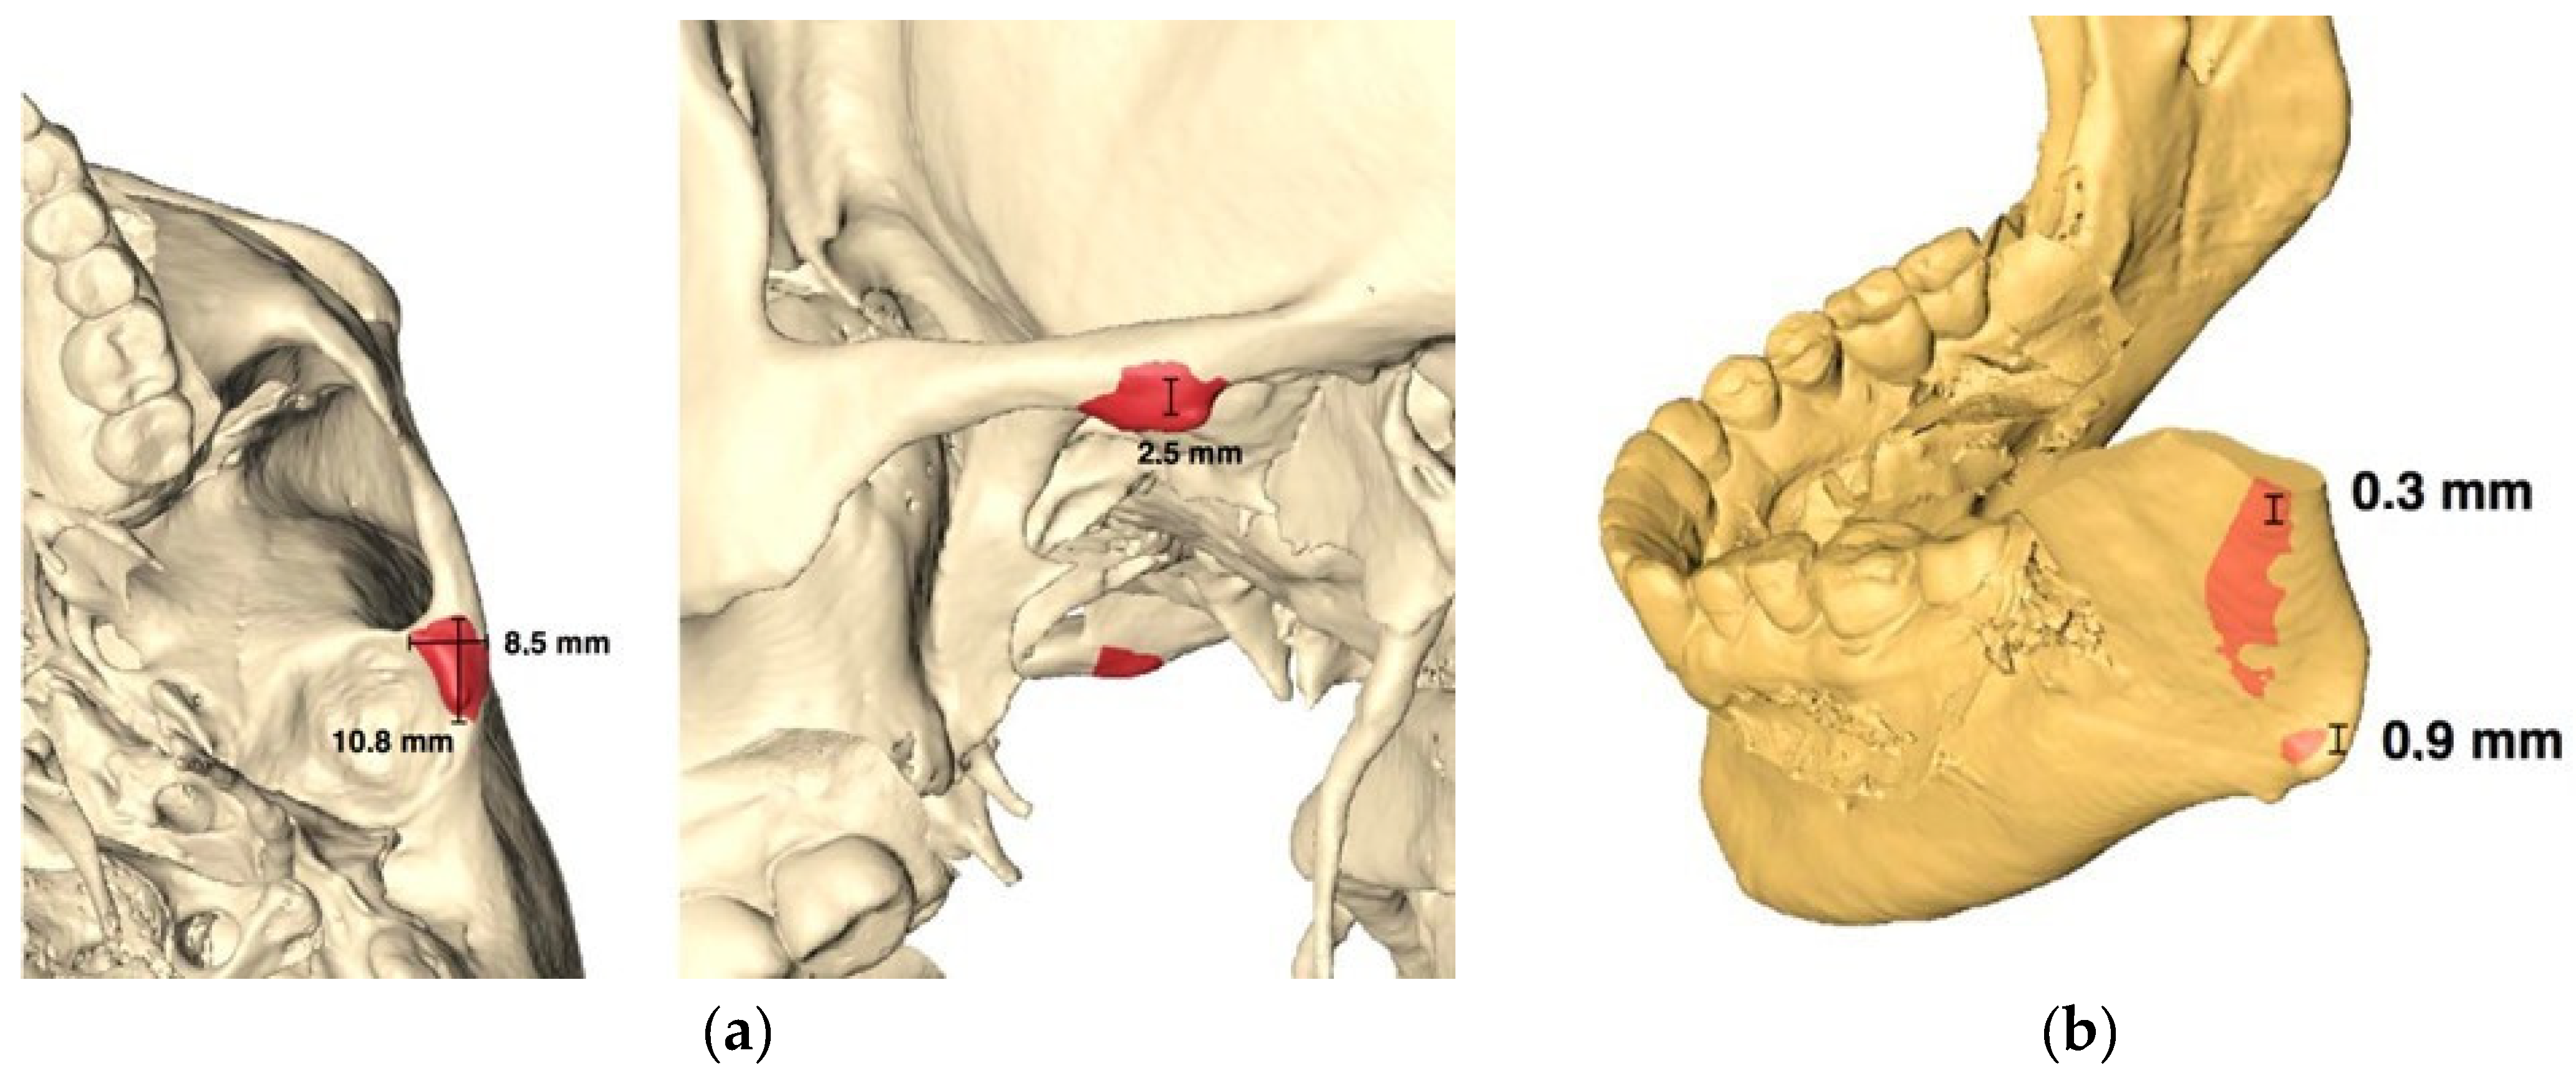

2.2. Preoperative Planning